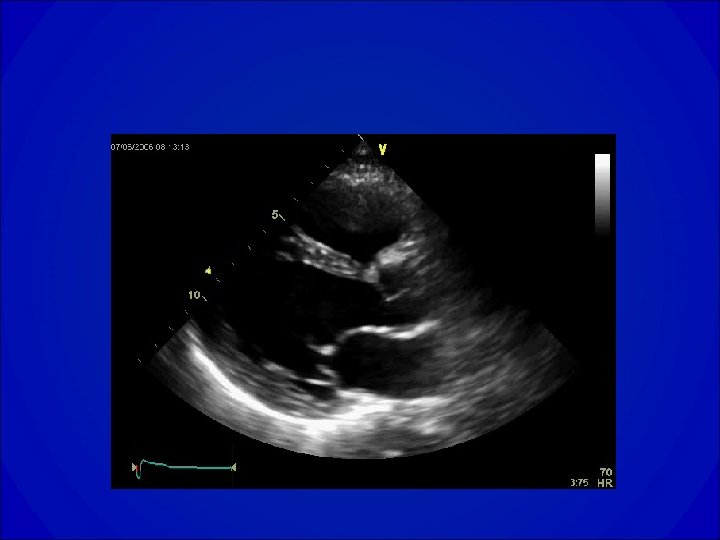

ECHOCARDIOGRAPHIE • Orientation étiologique et bilan de sévérité de la maladie • Evaluation de la fonction VG globale (dilatation ? Hypertrophie ? Fraction de raccourcissement, fraction d’éjection), cinétique segmentaire • Recherche d’une valvulopathie et évaluation de sa sévérité • Evaluation de la PAPS

Estimation des diamètres VG

VG normal Dysfonction VG

Echocardiogramme dans la RAo • Confirme un diagnostic clinique: épaississement ou calcification des valves dont l’ouverture est diminuée. • Apprécie le degré: gradient et surface (équation de continuité ou planimétrie en ETO). • Donne des renseignements étiologiques. • Apprécie le retentissement VG ( hypertrophie, fonction systolique et diastolique). • Recherche une valvulopathie associée et ou une pathologie de l’aorte ascendante.

Echo du RAo